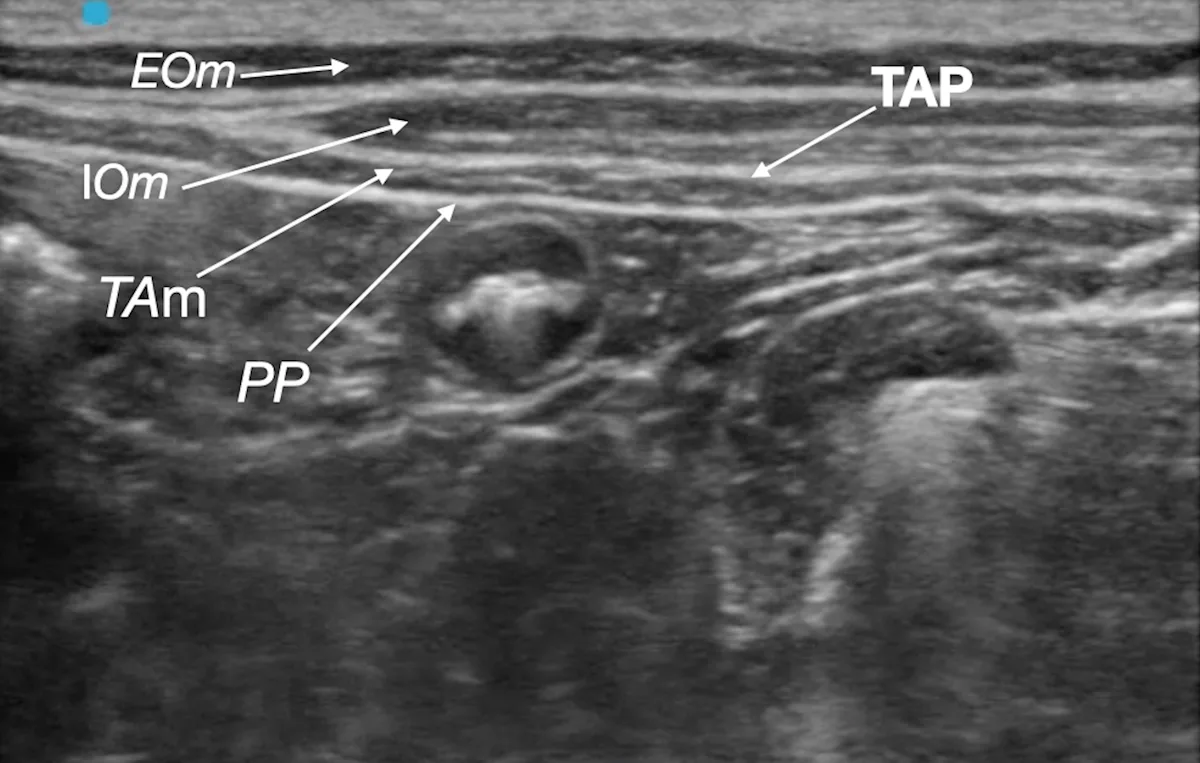

Step 8: Identify the Target Plane

Identify the target fascial plane (ie, TAP) as a hyperechoic line between the rectus abdominis muscle (RAm) and transversus abdominis muscle (TAm).

PP, parietal peritoneum

Step 9: Place the Needle for Cranial/Subcostal Block

Introduce the spinal needle in-plane, under the ultrasound beam through the rectus abdominis muscle. Direct the needle to the target fascial plane between the transversus abdominis and rectus abdominis muscles.

Author Insight

A pop sensation may be felt when the needle enters the target fascial plane.

Step 10: Confirm Needle Placement

Rule out intravascular needle placement via negative aspiration test, and inject a small aliquot of the local anesthetic (LA) to confirm hydrodissection of the target fascial plane (ie, TAP).

Having an assistant handle the syringe and inject the local anesthetic is recommended.

Step 11: Inject the Local Anesthetic for Cranial/Subcostal Block

Inject one aliquot (0.3 mL/kg) of the total calculated volume of the local anesthetic. Remove the spinal needle following injection.

The injected solution should separate the fascial plane, and anechoic fluid should be seen dissecting the fascia between the muscles. Gentle advancement of the needle into the target fascial plane during injection helps promote wider spread of the local anesthetic.